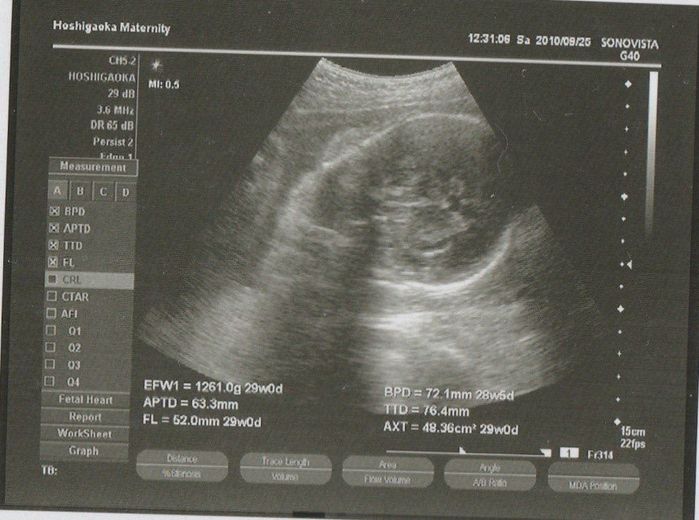

妊娠32週目のエコー写真

この週からいよいよ妊娠後期!またも頭部しか写っておりません。2週間ずつ健診はあるものの、エコーは4週間に一度しかなかったので、エコーを通して我が子を見ることができる貴重な時間でした。胎動がすごく、夜になるとゴニョゴニョと動き回っていました。